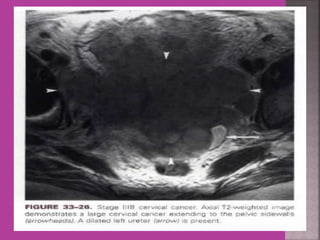

1. Cervical cancer –extent of parametrium

and pelvic organs , pelvic L.N., Endocervical.

 Gynaecological cancers--- 1. Cervical cancer –extent of parametrium and pelvic organs , pelvic L.N., Endocervical. 2.Endometrial cancer –Myometrial invasion, downward extension to cervix. 3. ovarian cancer—malignant versus benign mass, ascites , retroperitoneal node > 1cm , Bowel bladder , ano rectal . Parietal peritoneum , liver and or omental metastasis. 4. Pregnancy --- complicated by genital cancers

 MRI ismost sensitive for diagnosis of Adenomyosis.  MRI Is more accurate and informative in diagnosis of congenital malformation of genito-urinary tract.  Retroparitoneal lymph node > 1cm can be identified so also such small deposits on bowel / bladder liver can be identified in cases of cancers.  It is more sensitive and accurate tool to assess infiltration of myometrial/ cervical wall, adjoining organs and parametrium --thus helps in pre operative staging of genital carcinomas.  As it is safe in pregnancy –it is useful in diagnosis of obstetrical conditions as well s differentiation of tumors (benign / malignant ) complicating pregnancy.